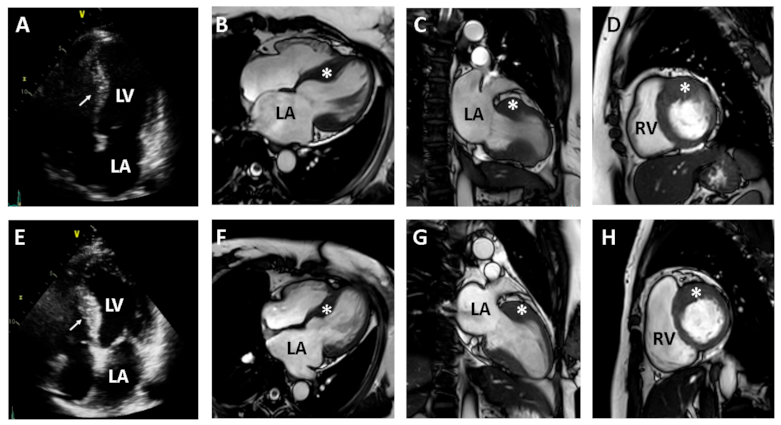

| Diagnosis | Restrictive cardiomyopathy | Hypertrophic cardiomyopathy | Hypertrophic cardiomyopathy |

| Sex/Age(year) | Male/74 | Female/44 | Female/41 |

| Electrocardiography and Holter monitoring | Atrial fibrillation and rare premature ventricular contractions | Sinus rhythm with frequent premature ventricular contractions | Sinus rhythm with rare premature atrial contractions and premature ventricular contractions |

| Transthoracic echocardiography | Biatrial enlargement and pericardial effusion | Asymmetric septal hypertrophy of LV and mildly dilated LA | Asymmetric septal hypertrophy of LV with mild LA enlargement |

| LVEDD 50 mm | LVEDD 40 mm | LVEDD 39 mm | |

| IVS 18 mm | IVS 17 mm | IVS 18.4 mm | |

| EF 60.2% | EF 64.2% | EF 64.2% | |

| E/e’ 14.1 | E/e’ 9 | E/e’ 10.1 | |

| e’ 5.2 cm/s | e’ 9.9 cm/s | e’ 7.5 cm/s | |

| TR peak velocity 3.8 m/s | TR peak velocity 1.8 m/s | TR peak velocity 2.5 m/s | |

| LAVI 115 mL/m2 | LAVI 41 mL/m2 | LAVI 40.1 mL/m2 |